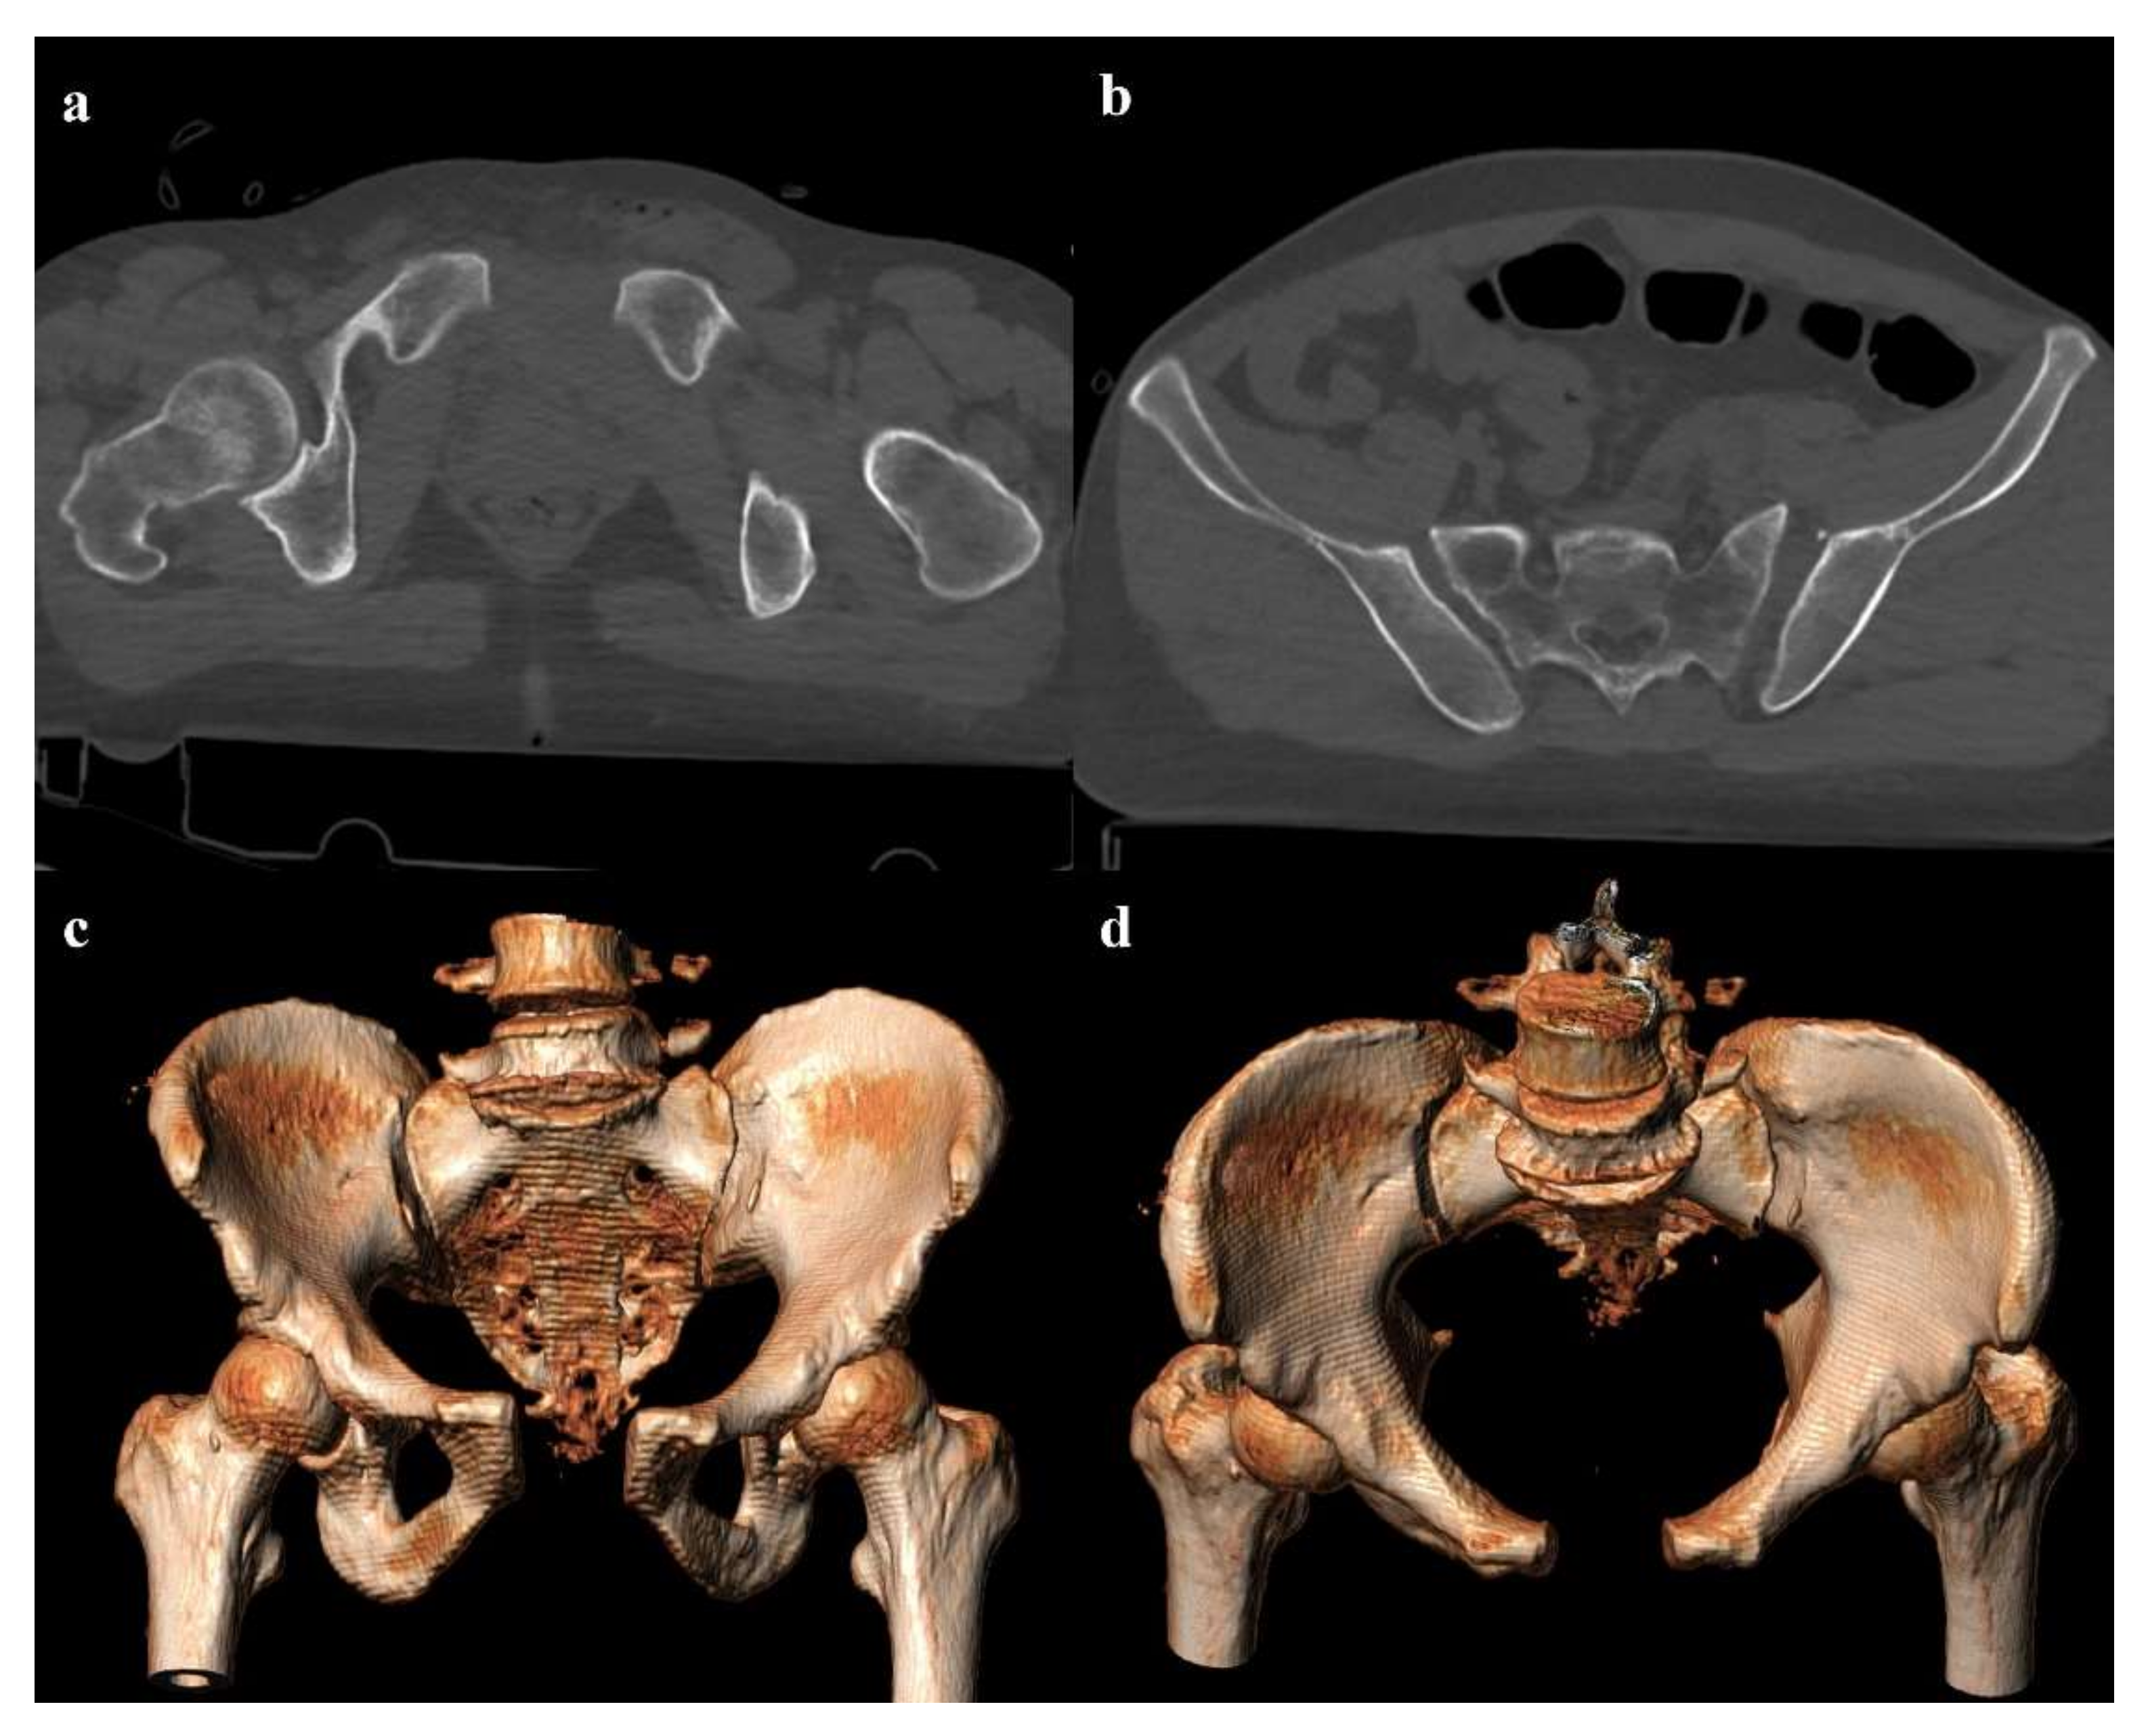

4.3. Young and Burgess Classification

4.3.1. Lateral Compression

- Grade 3: the lateral compression force is associated with a contralateral anteroposterior compression force, with an external rotation of the contralateral hemipelvis (“windswept pelvis”). Grade 1 or grade 2 lateral compression injuries are associated with a contralateral sacroiliac joint diastasis (Figure 3). Lateral compression grade 3 injuries have a multidirectional instability and require a stable internal fixation [3]. In these lesions, an adjunctive temporary external fixation is useful [3].